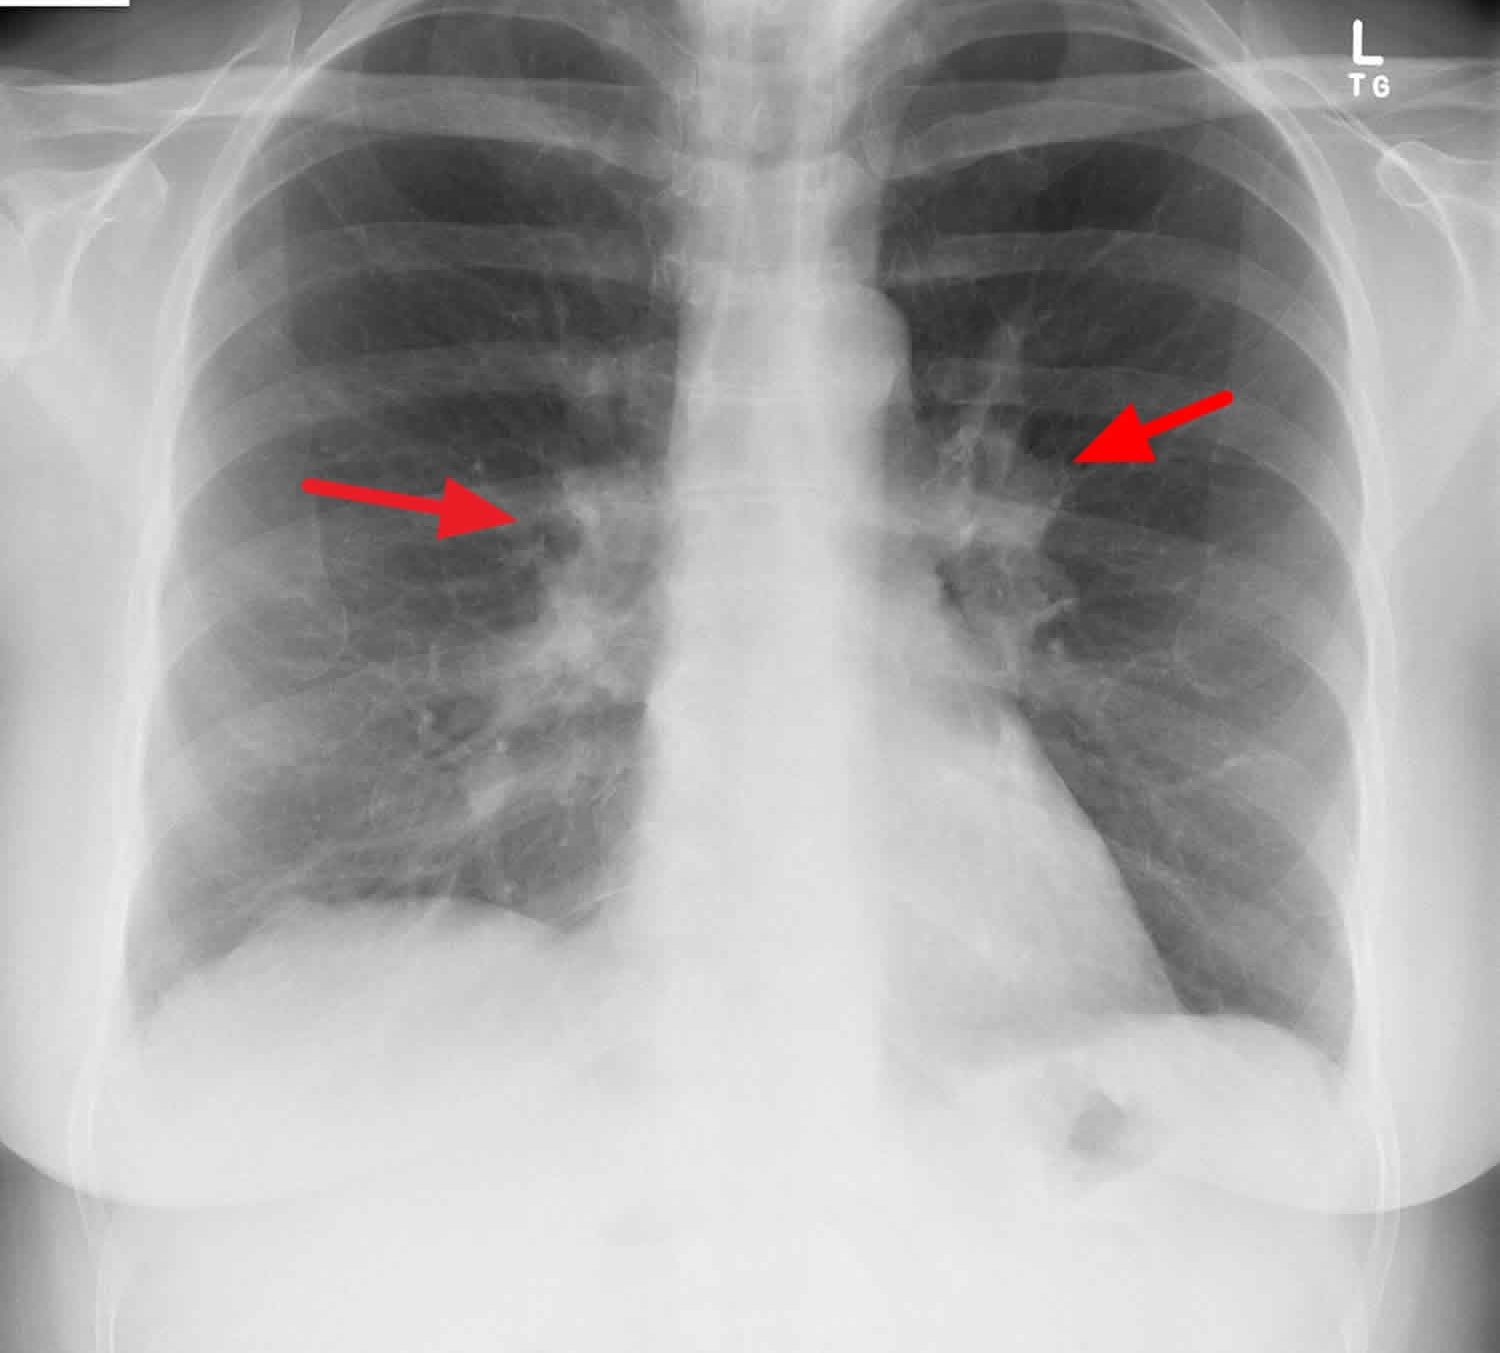

Right Hilar Lymph Node Enlargement

The enlargement of the right hilar lymph nodes is hilar adenopathy. Various factors are responsible for the expansion of the right hilar lymph node or hilar adenopathy in particular. Now, what are those factors or causes?

It may be caused; by infections such as mycoplasma, tuberculosis, histoplasmosis, and coccidioidomycosis. It may also be caused; by heart failure and sarcoidosis. Other causes include; inorganic dust diseases such as silicosis and berylliosis. It may be due to the result of malignancy, that is, carcinoma or lymphoma. Few individuals also report developing enlargement of this lymph node due to the consumption of drugs.

In unexplained conditions, imaging studies, tissue biopsy, and laboratory tests are recommended in identifying if any enlarged hilar lymph node is visible or not. However, imaging can easily recognize the distribution and size of the lymph node way more accurately than any examination method. Ultrasound is a non-invasive method to assess these nodes.